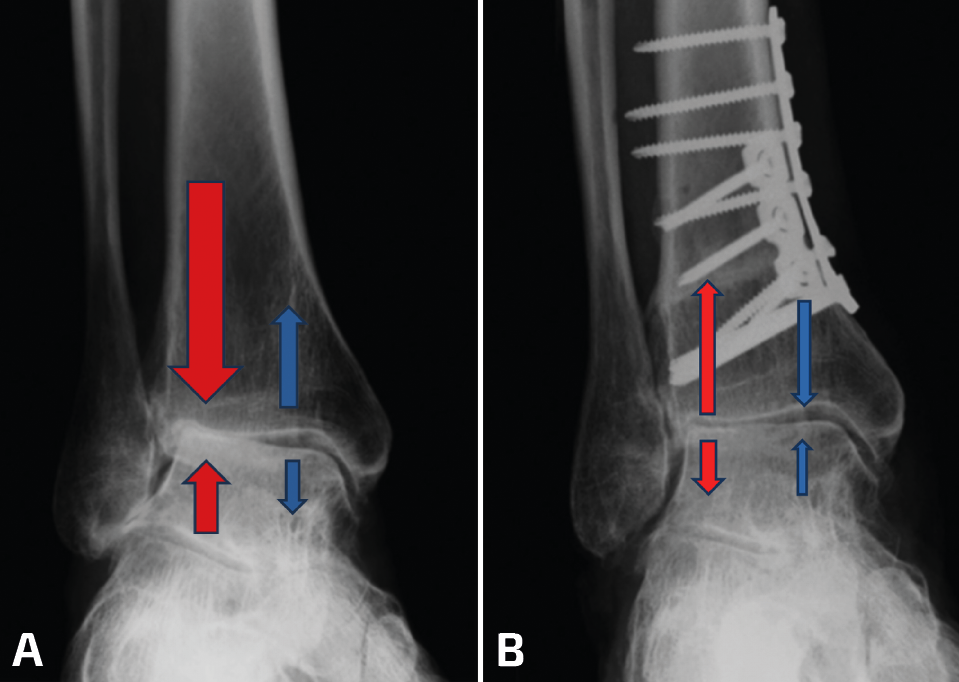

Cualquier alteración de la transmisión de cargas de la extremidad inferior puede producir una sobrecarga mecánica anormal y mantenida en el tobillo que puede llevar a una artrosis asimétrica. Cuando la transmisión de cargas se concentra en el área lateral del tobillo (región cóncava de la deformidad) se producirá un desgaste asimétrico de esa zona del tobillo (Figura 2).

Figura 2. A: alteración de cargas pre-osteotomía; B: osteotomía supramaleolar de cierre medial.

En los casos de malalineamiento en valgo, la OTT-SM debe lograr un efecto varizante. Esto se puede lograr con diferentes modelos de OTT; la más comúnmente utilizada es la OTT en cuña de cierre medial, que se realiza mediante un abordaje medial en la tibia distal, asociado o no a OTT de apertura en peroné (Figura 2).